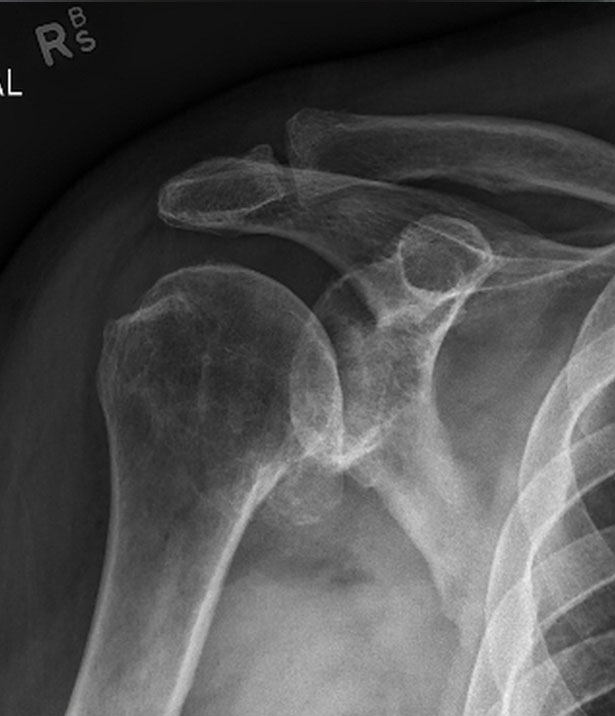

Shoulder before replacement surgery

Move the slider to compare arthritic shoulder with stemless replacement